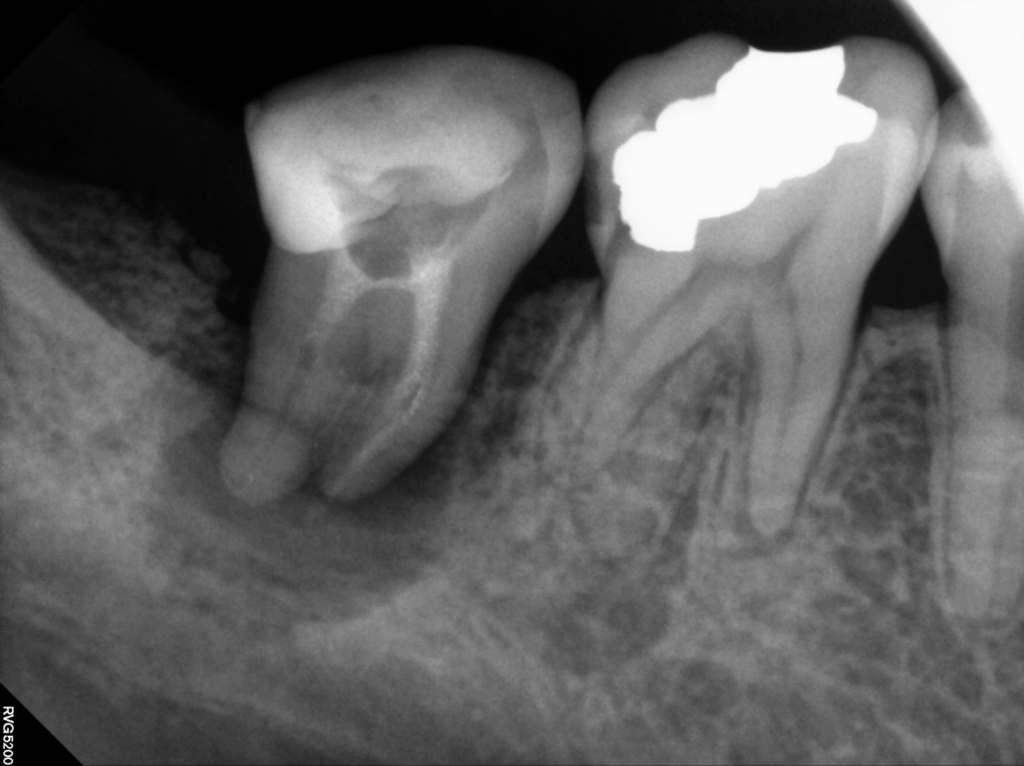

24.10.17

오랜 시간 전에 다른 치과에서 신경치료를 받으셨던 분으로, 최근 들어 해당 치아가 흔들리고 불편감이 심해져 방문해주신 사례입니다.

내원 당시 육안으로도 잇몸이 붓고 주변 조직이 예민한 모습이 보였으며, 정밀 촬영을 진행해보니 위 사진처럼 치근 주변에 어두운 음영의 병변이 분명하게 나타나고 있었습니다.

촬영 결과와 함께 치아 내부의 근관 상태도 면밀히 살펴본 결과, 초기 치료 과정에서 밀봉이 제대로 이루어지지 않아 세균이 다시 침투한 흔적을 확인할 수 있었고, 이에 따라 재근관치료가 필요하다고 판단하게 되었습니다.